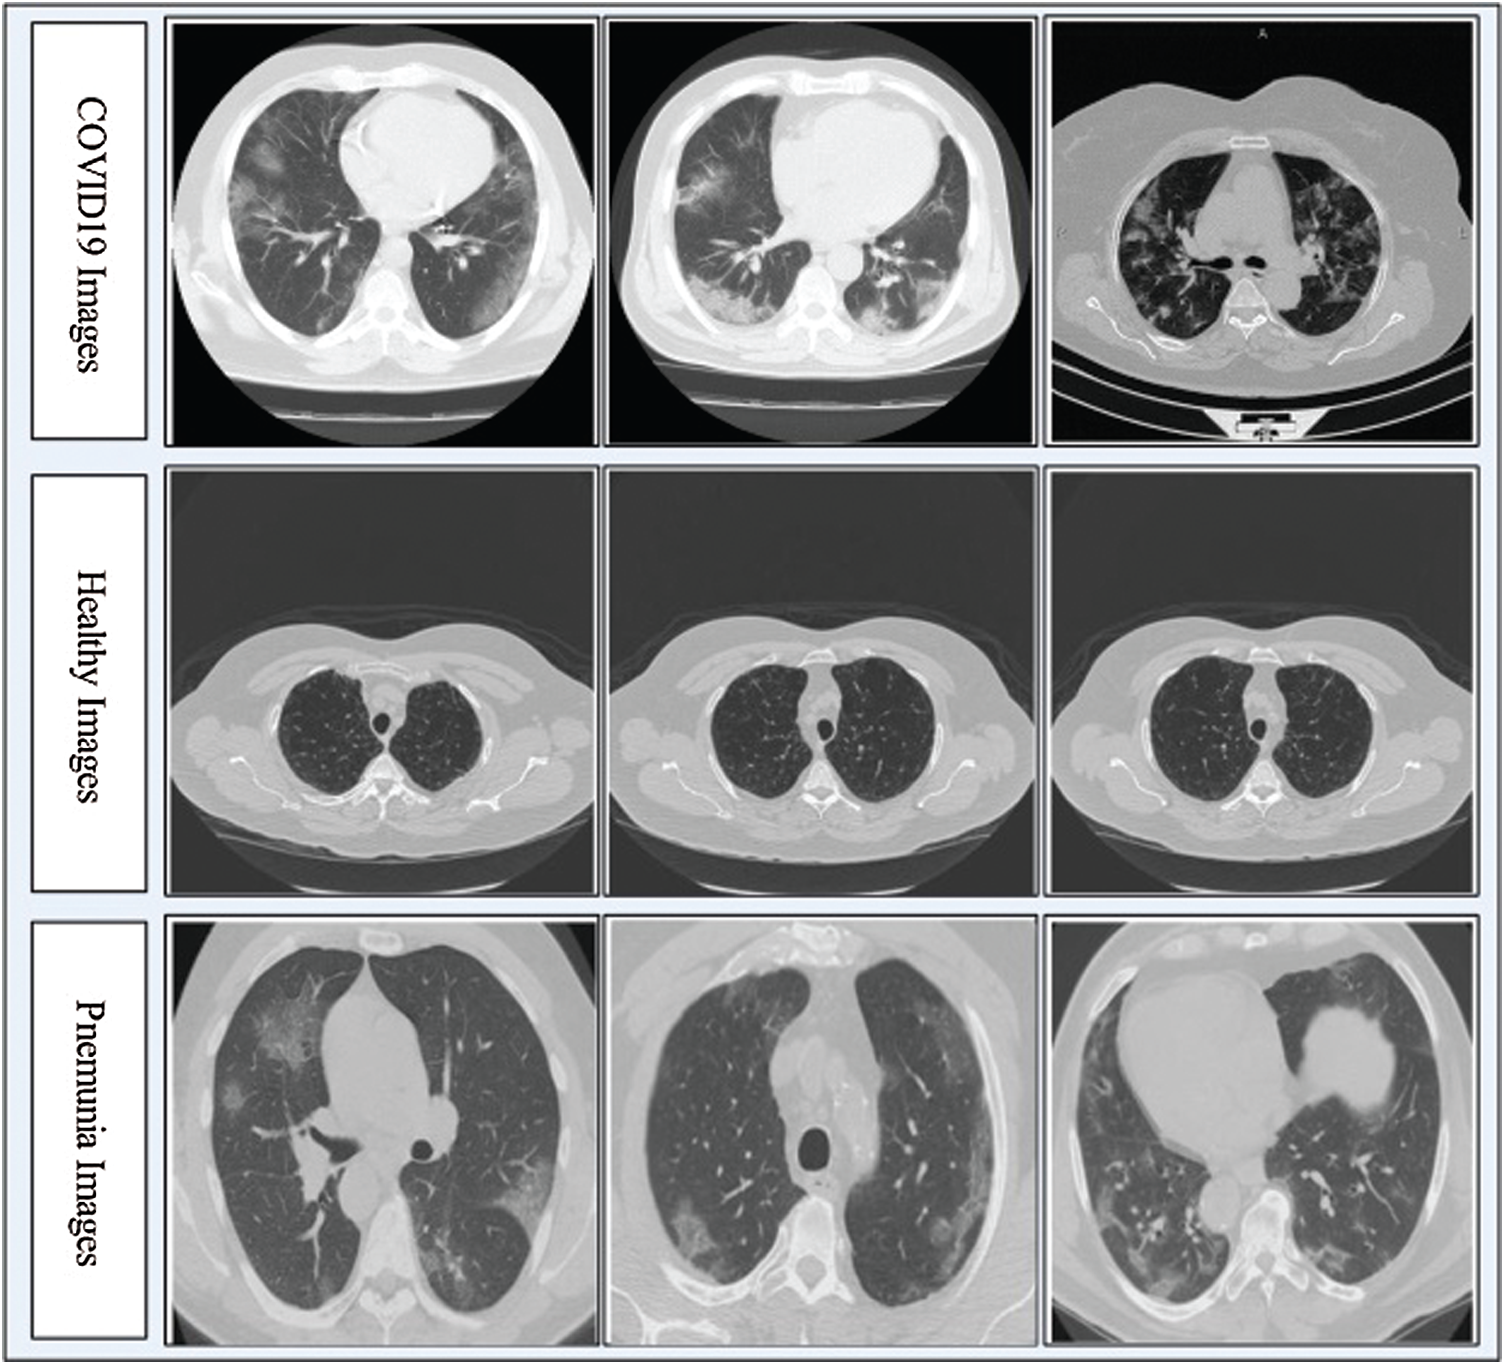

In this work, we collected a dataset from the Radiopaedia Website (https://radiopaedia.org). This website has CT images of more than 100 COVID-19-positive patients. We used the data from the first 80 patients, which included a total of 4000 CT images. Later, we collected 3000 CT images of healthy individuals and 2500 CT images of patients with pneumonia from the same website. Due to the imbalance in numbers between the classes, we performed data augmentation with horizontal flip and vertical flip operations. Mathematically, these flip operations are defined as follows:

Figure 2: Sample CT images of COVID19, Pneumonia, and Healthy